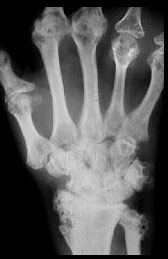

PUNCHED OUT LYTIC LESIONS LACY TRABECULAR PATTERN DEFORMING LESIONS

Advanced sarcoidosis with numerous osteolytic lesions of the distal forearm, wrist, and bones of the hand cause gross deformity.